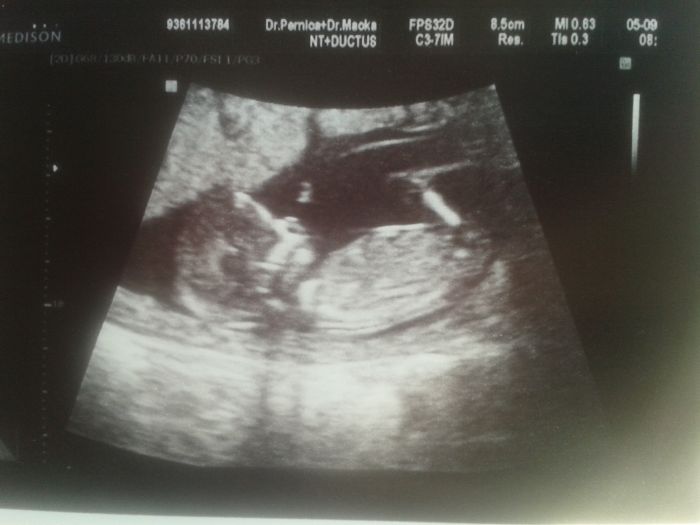

Ahoj holky, musím říct že jsem se trochu vyděsila, kdyz je tu řeč o tom porodu, mam z toho strach asi jako Kazda prvorodicka.. Chlapa mam naštěstí takovyho, ze kolikrát mi ani nedovoli neco uklízet :D ma svý mouchy to jistě ale je to vážně zlato... Dneska jsme byli na screeningu, byl z toho na měkko a ja taky :) prcek sebou házel jak o život a podle utz vse v pořádku, výsledky celkový posle dr emailem. Jinak pan doktor Pernica je úžasný :) Přikládám fotku :)